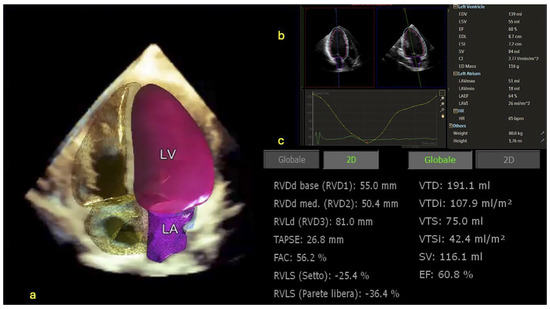

Cardiac Imaging Evolution: Artificial Intelligence-Guided Advancement